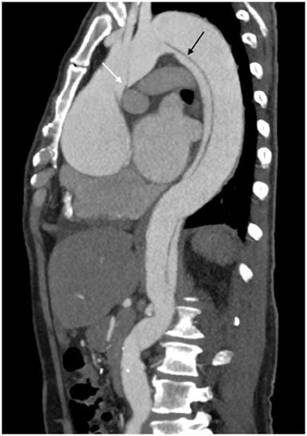

De acuerdo con la clasificación de Stanford, en nuestro estudio observamos que 17 pacientes (53.1%) fueron catalogados como Stanford A (fig. 4), mientras que los restantes 15 pacientes (46.9%) fueron catalogados como Stanford B (fig. 5). De acuerdo con la literatura, el subtipo Stanford A ocurre en el 60-70% de los casos6. En cuanto a la clasificación de De Bakey, el subtipo 3 fue el más frecuentemente diagnosticado, con 15 pacientes (46.9%), seguido del sub- tipo 1, que fue diagnosticado en 10 pacientes (31.2%), y del subtipo 2 en 7 pacientes (21.9%).

Figura 4 Caso de disección aórtica Stanford A/De Bakey 1. Paciente masculino de 53 años de edad con disección aórtica Stanford tipo A/De Bakey tipo 1. La flecha blanca indica el colgajo de disección a nivel de la aorta ascendente, y la flecha negra el colgajo de disección a nivel de aorta descendente que se extiende hasta el segmento abdominal.

sistémica, sin embargo, en nuestra muestra no se encontró asociación significativa con la DA por categorías de Stanford, con p no significativa, lo cual está probablemente relacionado con el tamaño de la muestra. Seguido de la hipertensión arterial, son de importancia los antecedentes de enfermedad ateroesclerótica calcificada de aorta (62.5%), el tabaquismo (56.3%) y el síndrome de Marfan (21%); este último sobre todo en pacientes jóvenes, ya que 4 pacientes de los 7 con antecedente de síndrome de Marfan se encuen- tran en el grupo etario entre los 20-29 años (57%). El síndrome de Marfan, causado por mutaciones del gen fibrilina- 1, tiene una prevalencia aproximada de 2-3 pacientes por cada 10,000 personas, causando dilatación gradual de la aorta que conlleva aneurisma y, finalmente, disección12,13. En esta población, el diámetro de los aneurismas es un factor importante a tomar en cuenta, ya que hay estudios que mencionan que el riesgo de muerte súbita o DA es bajo en pacientes con diámetros aórticos entre 45 y 49 mm, por lo que recomiendan cirugía profiláctica en diámetros aórticos mayores de 50 mm14. En pacientes con síndrome de Marfan de nuestra muestra, se presentó asociación con la DA por subtipos según la clasificación de Stanford con p marginal del 0.0506, siendo el 85% Stanford A. Según Tsai et al., lo más frecuente en esta población es la asociación con disección Stanford A